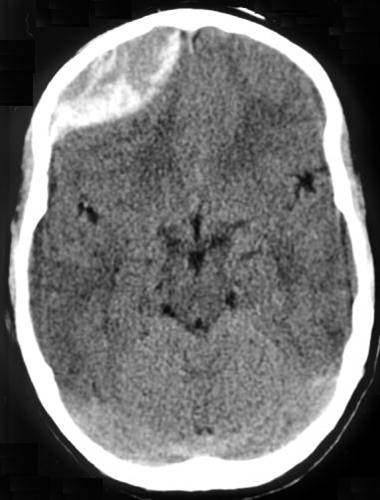

Radiology of epidural hematomas classically show a lens-shaped lesion representing the dura separated from the skull by hemorrhage.